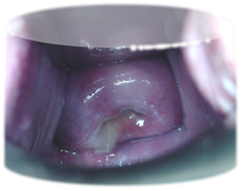

Chadwick’s sign

Bluish discoloration of cervix because of increased blood flow to cervix